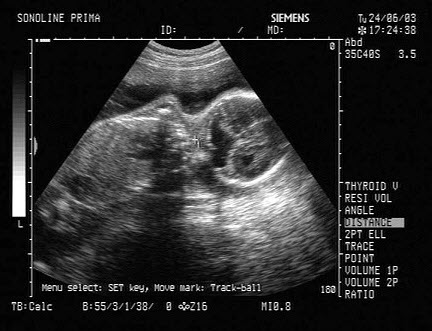

16、单项选择题

如图,正常甲状腺中部横切面的超声声像图,中央气管环状软骨前方组织为()

A.甲状腺峡部

B.皮下组织

C.甲状旁腺

D.淋巴结

E.以上均不对